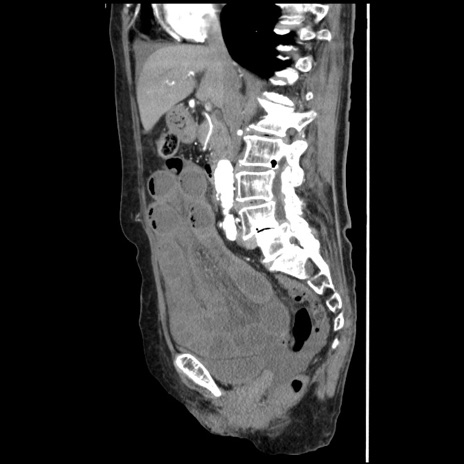

症例1(矢状断像)

【症例】80歳代女性

【主訴】腹痛

【現病歴】8時間前から腹痛あり来院。

【既往歴】糖尿病、脂質異常症、子宮体癌にて子宮全摘術

【身体所見】意識清明・会話良好だが腹痛で苦悶様、全腹部にわたって反跳痛と圧痛あり

【データ】WBC 13600、CRP 0.14、LDH 224、CK 90